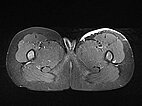

Axiale, T2-gewichtete, fettunterdrückte MRT des Patienten im Alter von 7 Jahren und 10 Monaten.

Das NICH noch sichtbar unter der Haut als hyperintense (weiße) flache Struktur, jedoch deutlich kleiner als vor der Embolisation.